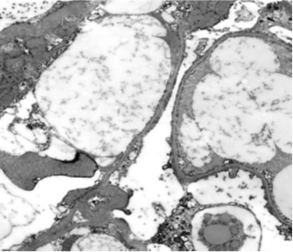

A 37-year-old female patient with hypothyroidism on 50 mcg levothyroxine once a day, a 6-month history of COVID-19 infection with residual loss of smell and taste, and a 1-week history of bilateral lower limb edema and puffiness of the eyes lids. When the patient's TSH level was discovered to be elevated, she was referred to an endocrinology clinic to have her levothyroxine maintenance dose modified. Urine albumin/creatinine ratio (2786 mg/g), total cholesterol 528 mg/dl, LDL 423.4 mg/dl, and triglyceride 174.5 mg/dl were all elevated. Additional confirmatory testing was carried out since nephrotic syndrome was highly suspected. A 24-hour urine protein collection revealed 4912 mg of protein excretion each day. Complement 3 (C3), complement 4 (C4), and erythrocyte sedimentation rate (E.S.R) were all within normal limits, indicating that post-streptococcal glomerulonephritis, membranoproliferative glomerulonephritis, and systemic lupus erythematosus (SLE) are unlikely, as complement levels are normally lowered in these disorders. A renal biopsy was performed, which revealed normal glomeruli by light microscopy Figure 1A, negative immunofluorescence, effacement of podocytes foot processes, and no viral particles by electron microscopy Figure 1B, confirming minimal change glomerulonephritis. The therapy with man-made corticosteroid (Prednisolone) 60 mg and Angiotensin- converting enzyme inhibitor (Ramipril) 5 mg once daily was effective in one month. The albumin/creatinine ratio fell from 2786.56 to 5.69 mg/g, urine microalbumin fell from 7278 to 11 mg/L, and total cholesterol fell from 528.3 to 215.4 mg/dl. The 24-hour urine protein measurement fell from 4912 to 91.8 mg/day. Laboratory testing demonstrated considerable improvement after three weeks of gradually tapering off oral steroids. The protein level in the urine was 82.6 mg/day, the microalbumin level was 7.6 mg/L, the albumin/creatinine ratio was 4.44 mg/g, and the protein in urine analysis was negative.

Figure 1A Light microscopy: The biopsy sample consists contain up to 21 glomeruli, 1 of them globally sclerosed. Glomerular basement membranes do not show thickening, spikes or vacuoles where tangentially cut. Adhesions, segmental sclerosis, hyalinosis, fibrin, necrosis or endocapillary proliferation or crescents are not seen. Tubular atrophy and interstitial scarring affect less than 5% of the cortex. Proximal tubular epithelium shows cytoplasmic vacuolation. Interstitium is free of inflammation. Seven interlobular arteries are included that show up to mild fibrointimal thickening. There is no arteriolosclerosis. Immunofluorescence Microscopy: sections were stained for C1q, C3, IgG, IgM, IgA, Kappa light chain & Lambda light chains, Fibrinogen and Albumin. All immunostains were negative.

Figure 1B Electron microscopy: Two glomeruli were available for assessment. The podocytes show cytoplasmic vacuolation & 90% effacement of the podocyte foot processes. Mesangial matrix is mildly increased without electron dense deposits. Occasional endothelial cells are swollen but their fenestrations are retained. Tubuloreticular inclusions are not detected. The tubular epithelial cells show cytoplasmic electron dense and clear droplets representing phagosomes with reabsorbed protein and lipid material. Small arteries are not sampled.